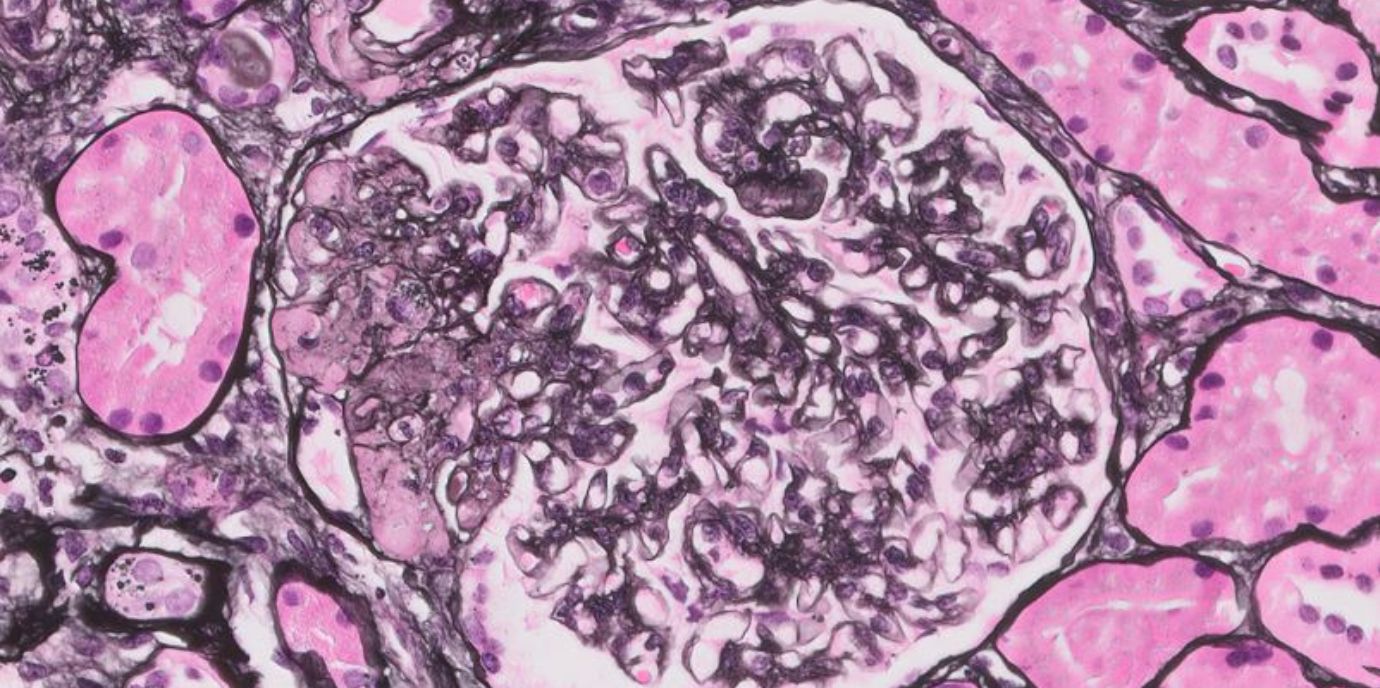

Vieles ist noch unerforscht bei Podozythopathien, zu denen die Formen Minimal Change Disease und FSGS (fokal segmentale Glomerulosklerose) zählen. Bei diesen seltenen Krankheiten werden die Filterzellen der Nieren (Podozyten) angegriffen. Wie viele Menschen davon betroffen sind, ist nicht genau bekannt. Vermutlich handelt es sich um Autoimmunerkrankungen. Es gibt starke Hinweise dafür. Doch auch das ist noch nicht restlos gesichert. Folglich gibt es keine zugelassene Therapie und schon gar keine, die auf die Ursache abzielen könnte. Jetzt aber stimmen die Ergebnisse einer retrospektiven Untersuchung, die an weltweit 30 Zentren in 15 Ländern und von insgesamt 52 ForscherInnen unter der Leitung von Philipp Gauckler (Erstautor) und Andreas Kronbichler (korrespondierender Autor) von der Univ.-Klinik für Innere Medizin IV (Direktor: Gert Mayer) durchgeführt wurde, zuversichtlich: In der Studie „Long-Term Outcomes of Rituximab-Treated Adult Patients with Podocythopathies“, die unlängst im hochrangigen Journal of the American Society of Nephrology veröffentlicht wurde, konnten die ForscherInnen zeigen, dass die Behandlung mit der Substanz Rituximab neben der guten Verträglichkeit noch weitere Vorteile für die PatientInnen bringt.

Außerdem: „Bei Kindern ist Minimal Change Disease mit mehr als 90 Prozent die allerhäufigste Ursache von einem nephrotischen Syndrom, sodass man ihre Nieren eigentlich schon gar nicht mehr biopsiert. Mit zunehmendem Alter tritt diese Krankheitsform aber weniger auf. Die FSGS-Erkrankung kommt über alle Altersgruppen hinweg in etwa stabil vor und ist für 20 Prozent der nephrotischen Syndrome verantwortlich“, erklärt Philipp Gauckler. Das Therapieansprechen bei FSGS ist meistens schlechter als bei Minimal Change Disease. Sprechen die PatientInnen auf die Therapie nicht an, werden sie nach durchschnittlich sieben Jahren dialysepflichtig, selbst nach einer Nierentransplantation kehren in 30 bis 40 Prozent der Fälle die Krankheitsschübe zurück. „Auch deshalb geht man davon aus, dass es sich um eine Autoimmunerkrankung handelt. Wäre die Krankheit nierenassoziiert, würde es im Transplantat keine Rückfälle geben“, führt Andreas Kronbichler weiter aus.